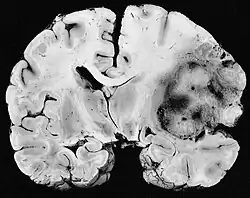

Neurofibrosarcoma, um tipo de sarcoma altamente maligno e deformante.

Um sarcoma é um cancro (câncer)/neoplasia que atinge células da mesoderme, em contraste com os cânceres mais comuns, que atingem a parte mais superficial ou interna do tecido. Pode atingir osso, cartilagem, gordura, músculo, vasos sanguíneos, ou tecidos moles. O termo advém do termo grego e significa "crescimento carnoso". São os tipos de câncer que mais fazem metástase e portanto os mais perigosos e difíceis de serem tratados. [1]